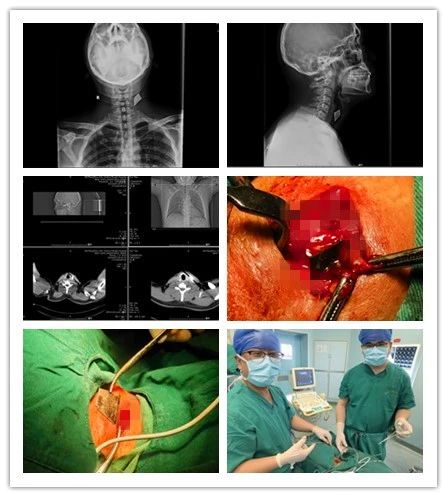

近日,一位“美工刀”刀刺傷的患者來(lái)我院乳腺甲狀腺外科就診,頸部正側(cè)位拍片顯示“美工刀片”深入頸深部,嚴(yán)重危及生命。乳腺甲狀腺外科團(tuán)隊(duì)以十分鐘的“小手術(shù)”成功為患者解除危機(jī),患者現(xiàn)已痊愈出院。

患者,男,35歲,3個(gè)月前頸部被銳器刺傷,傷后出血量約50ml,伴有疼痛,不伴有麻木,呼吸正常,于外院行清創(chuàng)縫合手術(shù),術(shù)后切口反復(fù)感染,并伴有頸部及左側(cè)上肢放射性疼痛,后于我院復(fù)查頸部正側(cè)位片示左側(cè)頸前不規(guī)則致密影,門(mén)診以“左頸部異物”收入院。

乳腺甲狀腺外科王思雷和楊汶士主治醫(yī)師接診后,追問(wèn)患者病史并仔細(xì)檢查,確認(rèn)患者皮膚淺層不存在異物,認(rèn)為異物存在于頸深部,且異物為銳器“美工刀片”,有傷及頸部大血管及氣管、食管可能,隨時(shí)危機(jī)生命,建議手術(shù)取出。但異物位置深,緊鄰頸部大血管、氣管、食管,存在較大手術(shù)難度和風(fēng)險(xiǎn)??浦魅卫罘搴屯跛祭住钽胧恐髦吾t(yī)師進(jìn)行充分術(shù)前討論后,制定了周密的手術(shù)方案,在彩超及C臂機(jī)引導(dǎo)下,精確定位,為患者施行頸部異物取出術(shù)+清創(chuàng)縫合術(shù)。術(shù)中發(fā)現(xiàn)異物為銳器“美工刀片”,刀刃鋒利,位置深達(dá)頸椎前側(cè),緊鄰頸部大血管及氣管、食管,差之毫厘便可能造成血管破裂致大出血。兩位醫(yī)師憑借嫻熟的技術(shù),小心翼翼探查,僅用十分鐘便成功取出異物。